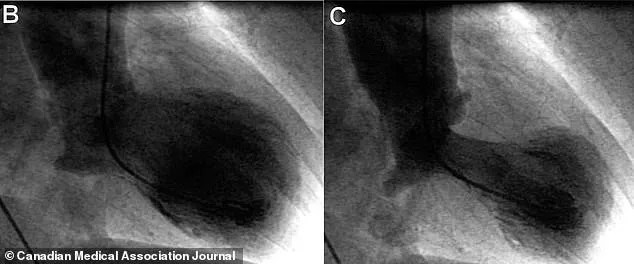

Symptoms of broken heart syndrome are deceptively similar to those of a heart attack. Patients often experience crushing chest pain, shortness of breath, dizziness, and even fainting. These symptoms are so severe that they frequently lead to emergency room visits. However, unlike a heart attack, the syndrome does not result from blocked coronary arteries. Instead, it is marked by a temporary weakening of the heart muscle, often resembling an octopus pot—a shape that gives the condition its Japanese name, takotsubo. This distinctive heart shape, captured through echocardiograms, is a critical diagnostic marker that helps distinguish the syndrome from a true heart attack.

Diagnosing broken heart syndrome is a delicate process. Doctors must first rule out a heart attack, which involves invasive procedures like cardiac catheterization. This process, though effective, can be time-consuming and stressful for patients. Once a heart attack is excluded, the presence of a distinctive heart shape on an echocardiogram and elevated troponin levels in the blood confirm the diagnosis. Troponin, a protein released when heart muscle is damaged, is a key biomarker in distinguishing the syndrome from other cardiac conditions.